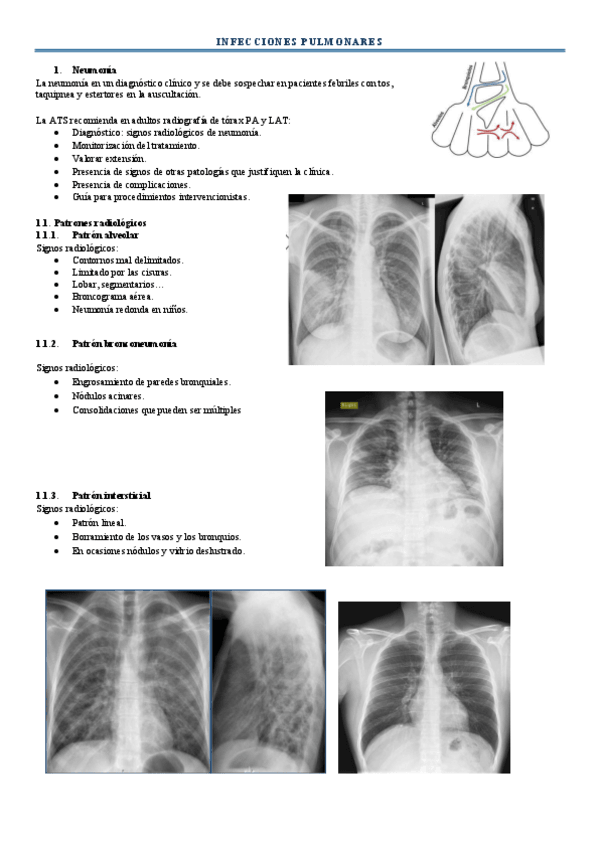

He publicado nuevos apuntes de 3º Radiología y Medicina Física. Protección Radiológica: seminario-ire-infecciones.pdf

60 páginas